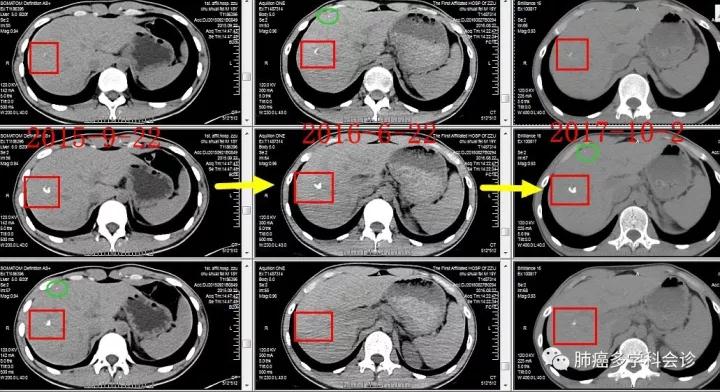

此患者在初诊时就发现了肝内两个小钙化灶,在过去的3年内没有变化,考虑良性病变。

4. 该患者的肝内两个小钙化灶在初诊是就有,长期没有变化,也起到了一定的麻痹医生的作用。